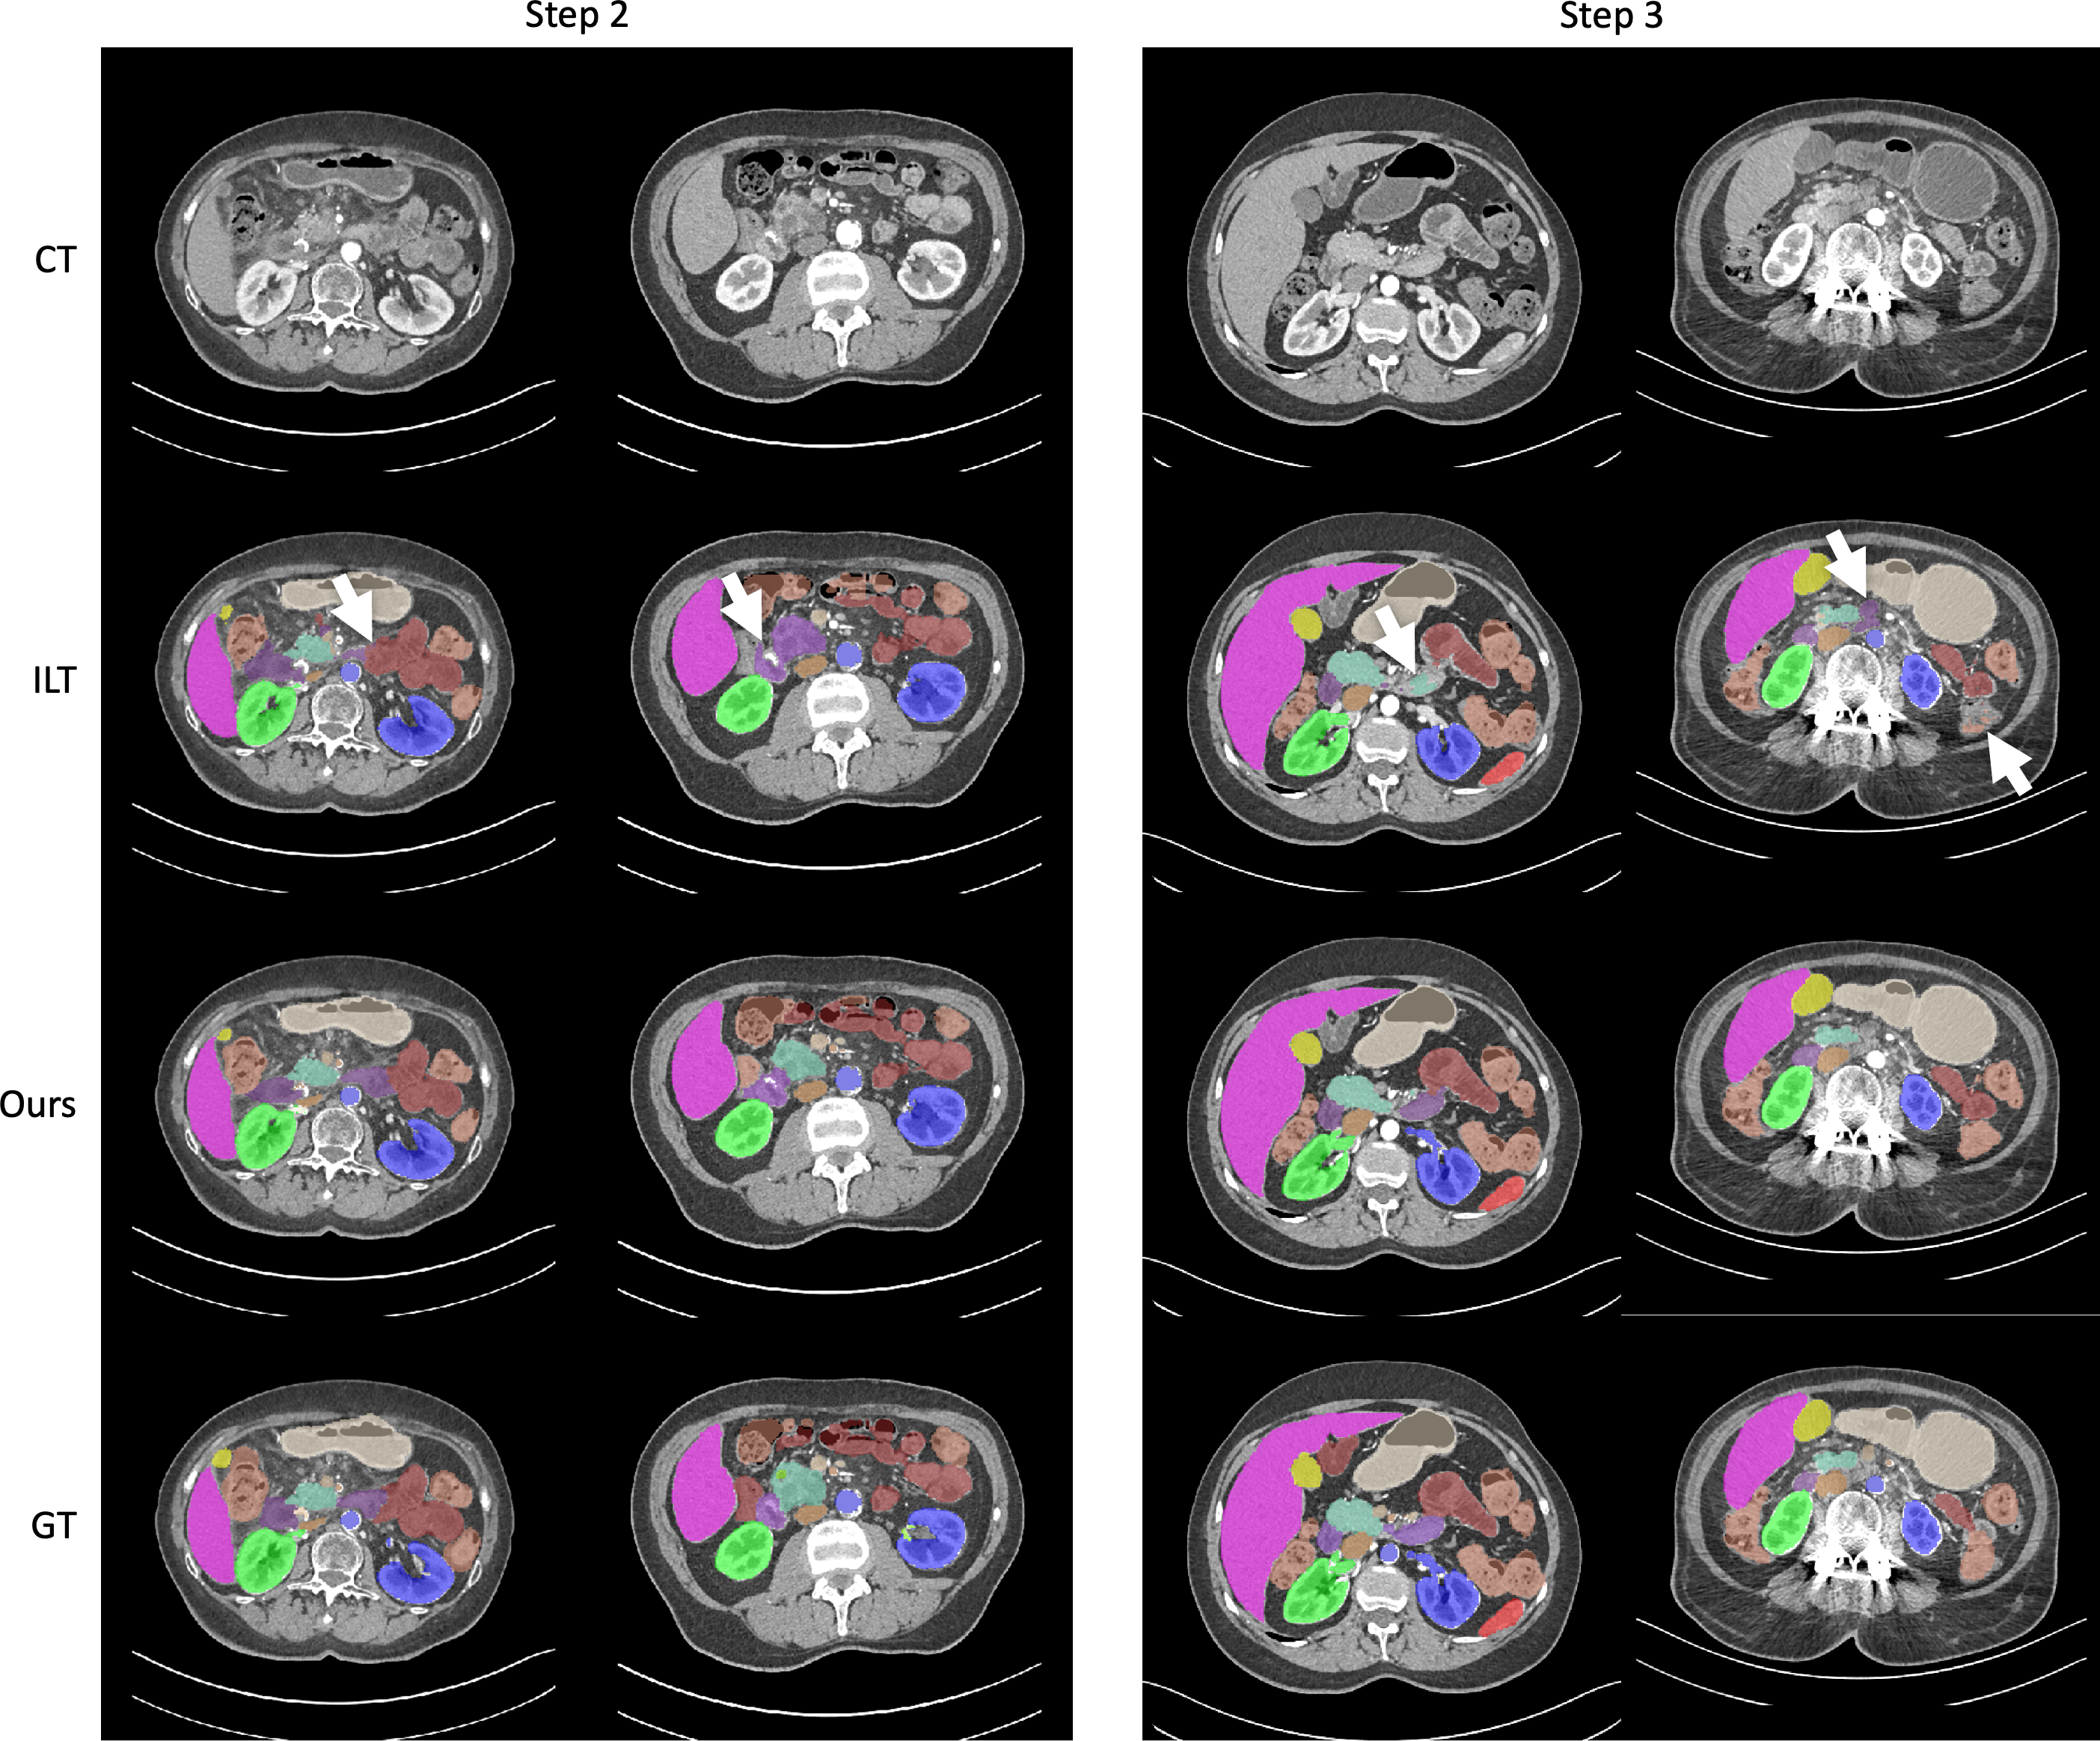

Finally, we show the qualitative segmentation results of the proposed method together with the best baseline method ILT on the JHH dataset. We show the results of learning steps 2 and 3 in Figure 2, one case per column and two cases for each step. The visualization demonstrates that the proposed method successfully segments the correct organs while the best baseline method fails throughout the continual learning process.